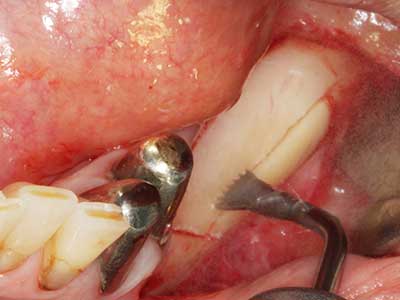

Piezosurgery has additional advantages when harvesting bone blocks. In addition to the high precision with osteotomy described above, the use of the thin saw tips specifically minimizes loss of material. Greater loss of material during harvesting can be expected with the thicker instrument tips, particularly when using Lindemann drills (Lakshmiganthan, Gokulanathan et al. 2012). The basal separation, which is necessary particularly for retromolar block transplants, is simplified by specially designed rectangular saws, with the result that piezosurgery is viewed as a precise, simple and safe procedure for harvesting retromolar bone blocks (Happe 2007) (Fig. 1-12).

Fig. 1: Preparation of a bone cover with the Piezomed (W&H Salzburg, Austria).

Fig. 3: Basal separation of the block is easier with specially angled attachments.